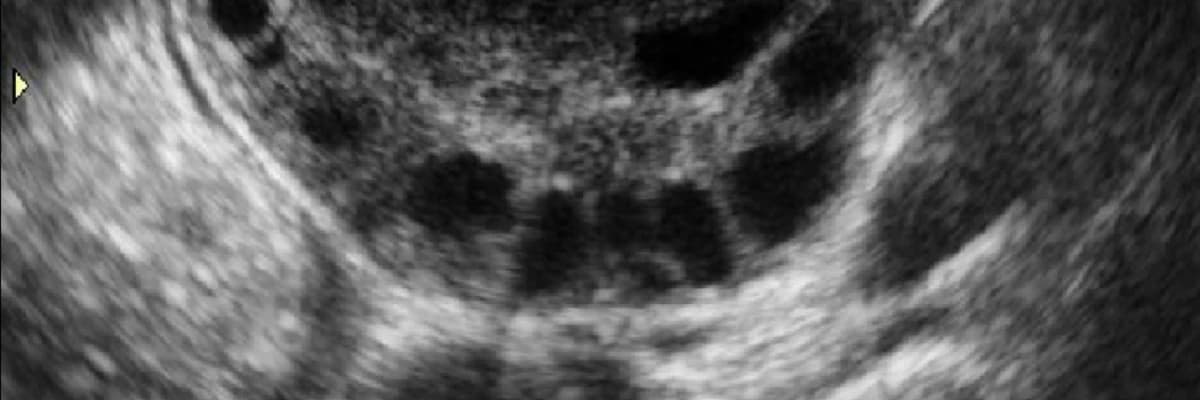

Polikistik over görünümü ultrason ile değerlendirildiğinde kadınların yumurtalıklarını tanımlayan bir terim olmaktadır. Bir overde 12 ya da daha fazla 2 ile 8 mm arasında değişen kistler bulunmaktadır. Bu durum her zaman sorun anlamına gelmemektedir ve sadece ultrasonografik bir bulgudan ibaret olabilir.

Polikistik over sendromu tanımı çoğu zaman yanlış anlaşılarak ve yumurtalıklarda kist var sanılmaktadır. Fakat burada asıl anlatılmak istenilen yumurtalıklarda gerçek anlamda kistlerin varlığı değil, gelişimini tamamlayamayıp 2-8 mm boyutunda kalan ve sayıları artan erken yumurtalardır.